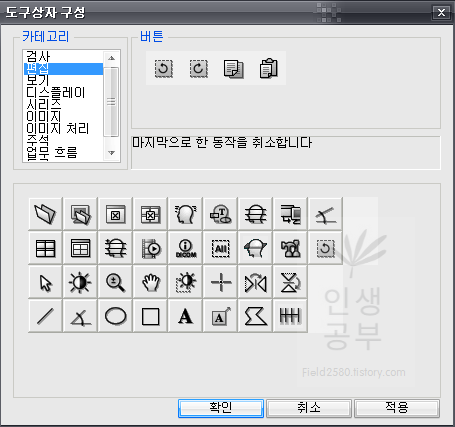

마지막으로 한 동작을 취소합니다 버튼이 추가 된 것을 확인하실 수 있습니다.

그 후에 2번째 칸에 있는 이전에 취소한 동작을 다시 수행합니다 버튼을 추가해줍니다.

두 번째 버튼을 클릭하고 아래로 드래그해서 내려주면 아래 도구상자에 추가됩니다.참고로 위의 두 버튼은 단축키를 알아두시면 훨씬 편하게 사용하실 수 있습니다. 단축키가 익숙해지면 도구상자 메뉴에서 삭제해도 상관없습니다. 하지만 익숙해지기 전까지는 도구상자 메뉴에 넣어두시는 걸 추천해 드립니다.